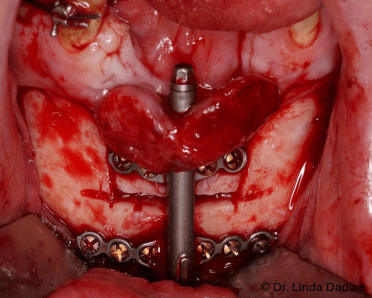

Nach umfassender Aufklärung erfolgte – aufgrund des unzureichenden Knochen- und Weichgewebsangebots für eine unmittelbare Implantation – eine Unterkieferdistraktion zur vertikalen Augmentation des Knochens und zur Vermehrung des Weichgewebes durch eine kontinuierliche Dehnung. In Intubationsnarkose wurde der Knochendefekt dargestellt und das Segment in Regio 32-42 osteotomiert. Das Segment war an der lingualen Schleimhaut gestielt, mobilisiert und gut durchblutet. Anschließend wurde der Distraktor (KLS Martin) angepasst und eingebracht (Abb. 2a–c). Abschließend erfolgten der Wundverschluss und eine postoperative Röntgenkontrolle (Abb. 3).